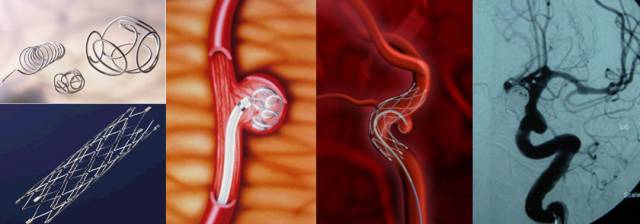

属于介入治疗方法,采取经皮穿刺股(或颈)动脉,插入导引管,再经导引管插入微导管至动脉瘤内或载瘤动脉,经微导管送入栓塞材料(如球囊、微弹簧圈),将动脉瘤或载瘤动脉闭塞的方法。–此方法创伤小、效果佳、术后恢复快。

适用于:

①急性蛛网膜下腔出血的早期,病情的趋向不明确;

②病情严重的病例不允许作开颅手术,或手术需延迟进行;

③动脉瘤位于手术不能达到的部位;

④拒绝手术治疗或等待手术治疗的病例。